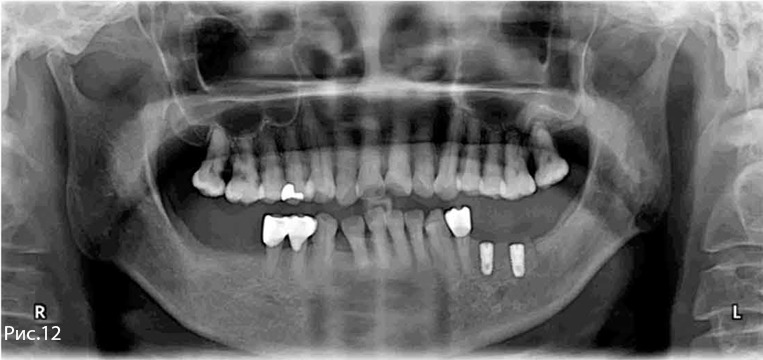

Рис. 1—2. Исходная рентгенологическая и клиническая картина.

Рис. 1—2. Исходная рентгенологическая картина.